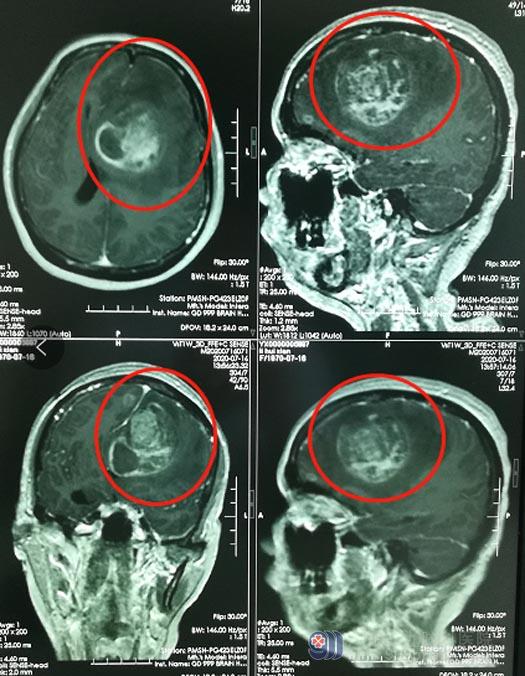

50岁的李阿姨,一个月前出现神志不清,并进行性加重,同时伴有右侧肢体乏力,后逐渐出现不能行走、不能言语、喷射性呕吐等症状,当地医院头颅CT检查提示“左侧额顶叶占位,伴出血,考虑肿瘤卒中”,肿瘤多发且体积较大,并且累及血管;看着一直在摇头的医生,家人决定立刻转院。

辗转来到广东三九脑科医院神经外五科后,进一步颅脑CT检查发现:1.左侧额叶占位性病变并卒中,考虑转移瘤并卒中;2.双侧额颞叶及左侧基底节区多发转移瘤;3.左侧大脑镰下疝、左侧海马钩回疝。此时的李阿姨已经浅昏迷,GCS评分10分,脑疝形成。